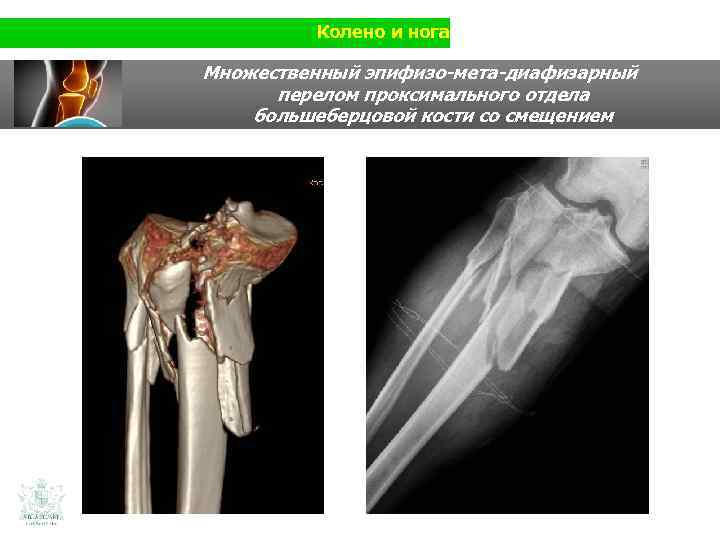

Колено и нога Клинический случай (колено и нога) Мужчина 56 лет Травма нижней конечности на мотоцикле Использования изображения в 3 D

Колено и нога Множественный эпифизо-мета-диафизарный перелом проксимального отдела большеберцовой кости со смещением

Колено и нога Множественный эпифизо-мета-диафизарный перелом проксимального отдела большеберцовой кости со смещением Изображение в 3 D (масштаб 1: 1) Использование изображения в 3 D способствует изучению перелома, его анализа в 3 хмерном измерении, для оптимальной подготовки к операции. Изображение в 3 D при сложных суставных переломах. Возожность реконструкции в 3 D позволяет изучить перелом. Настоящей революцией является то, что врач и пациент имеют возможность потрогать рукой пораженную часть кости во время исследования .